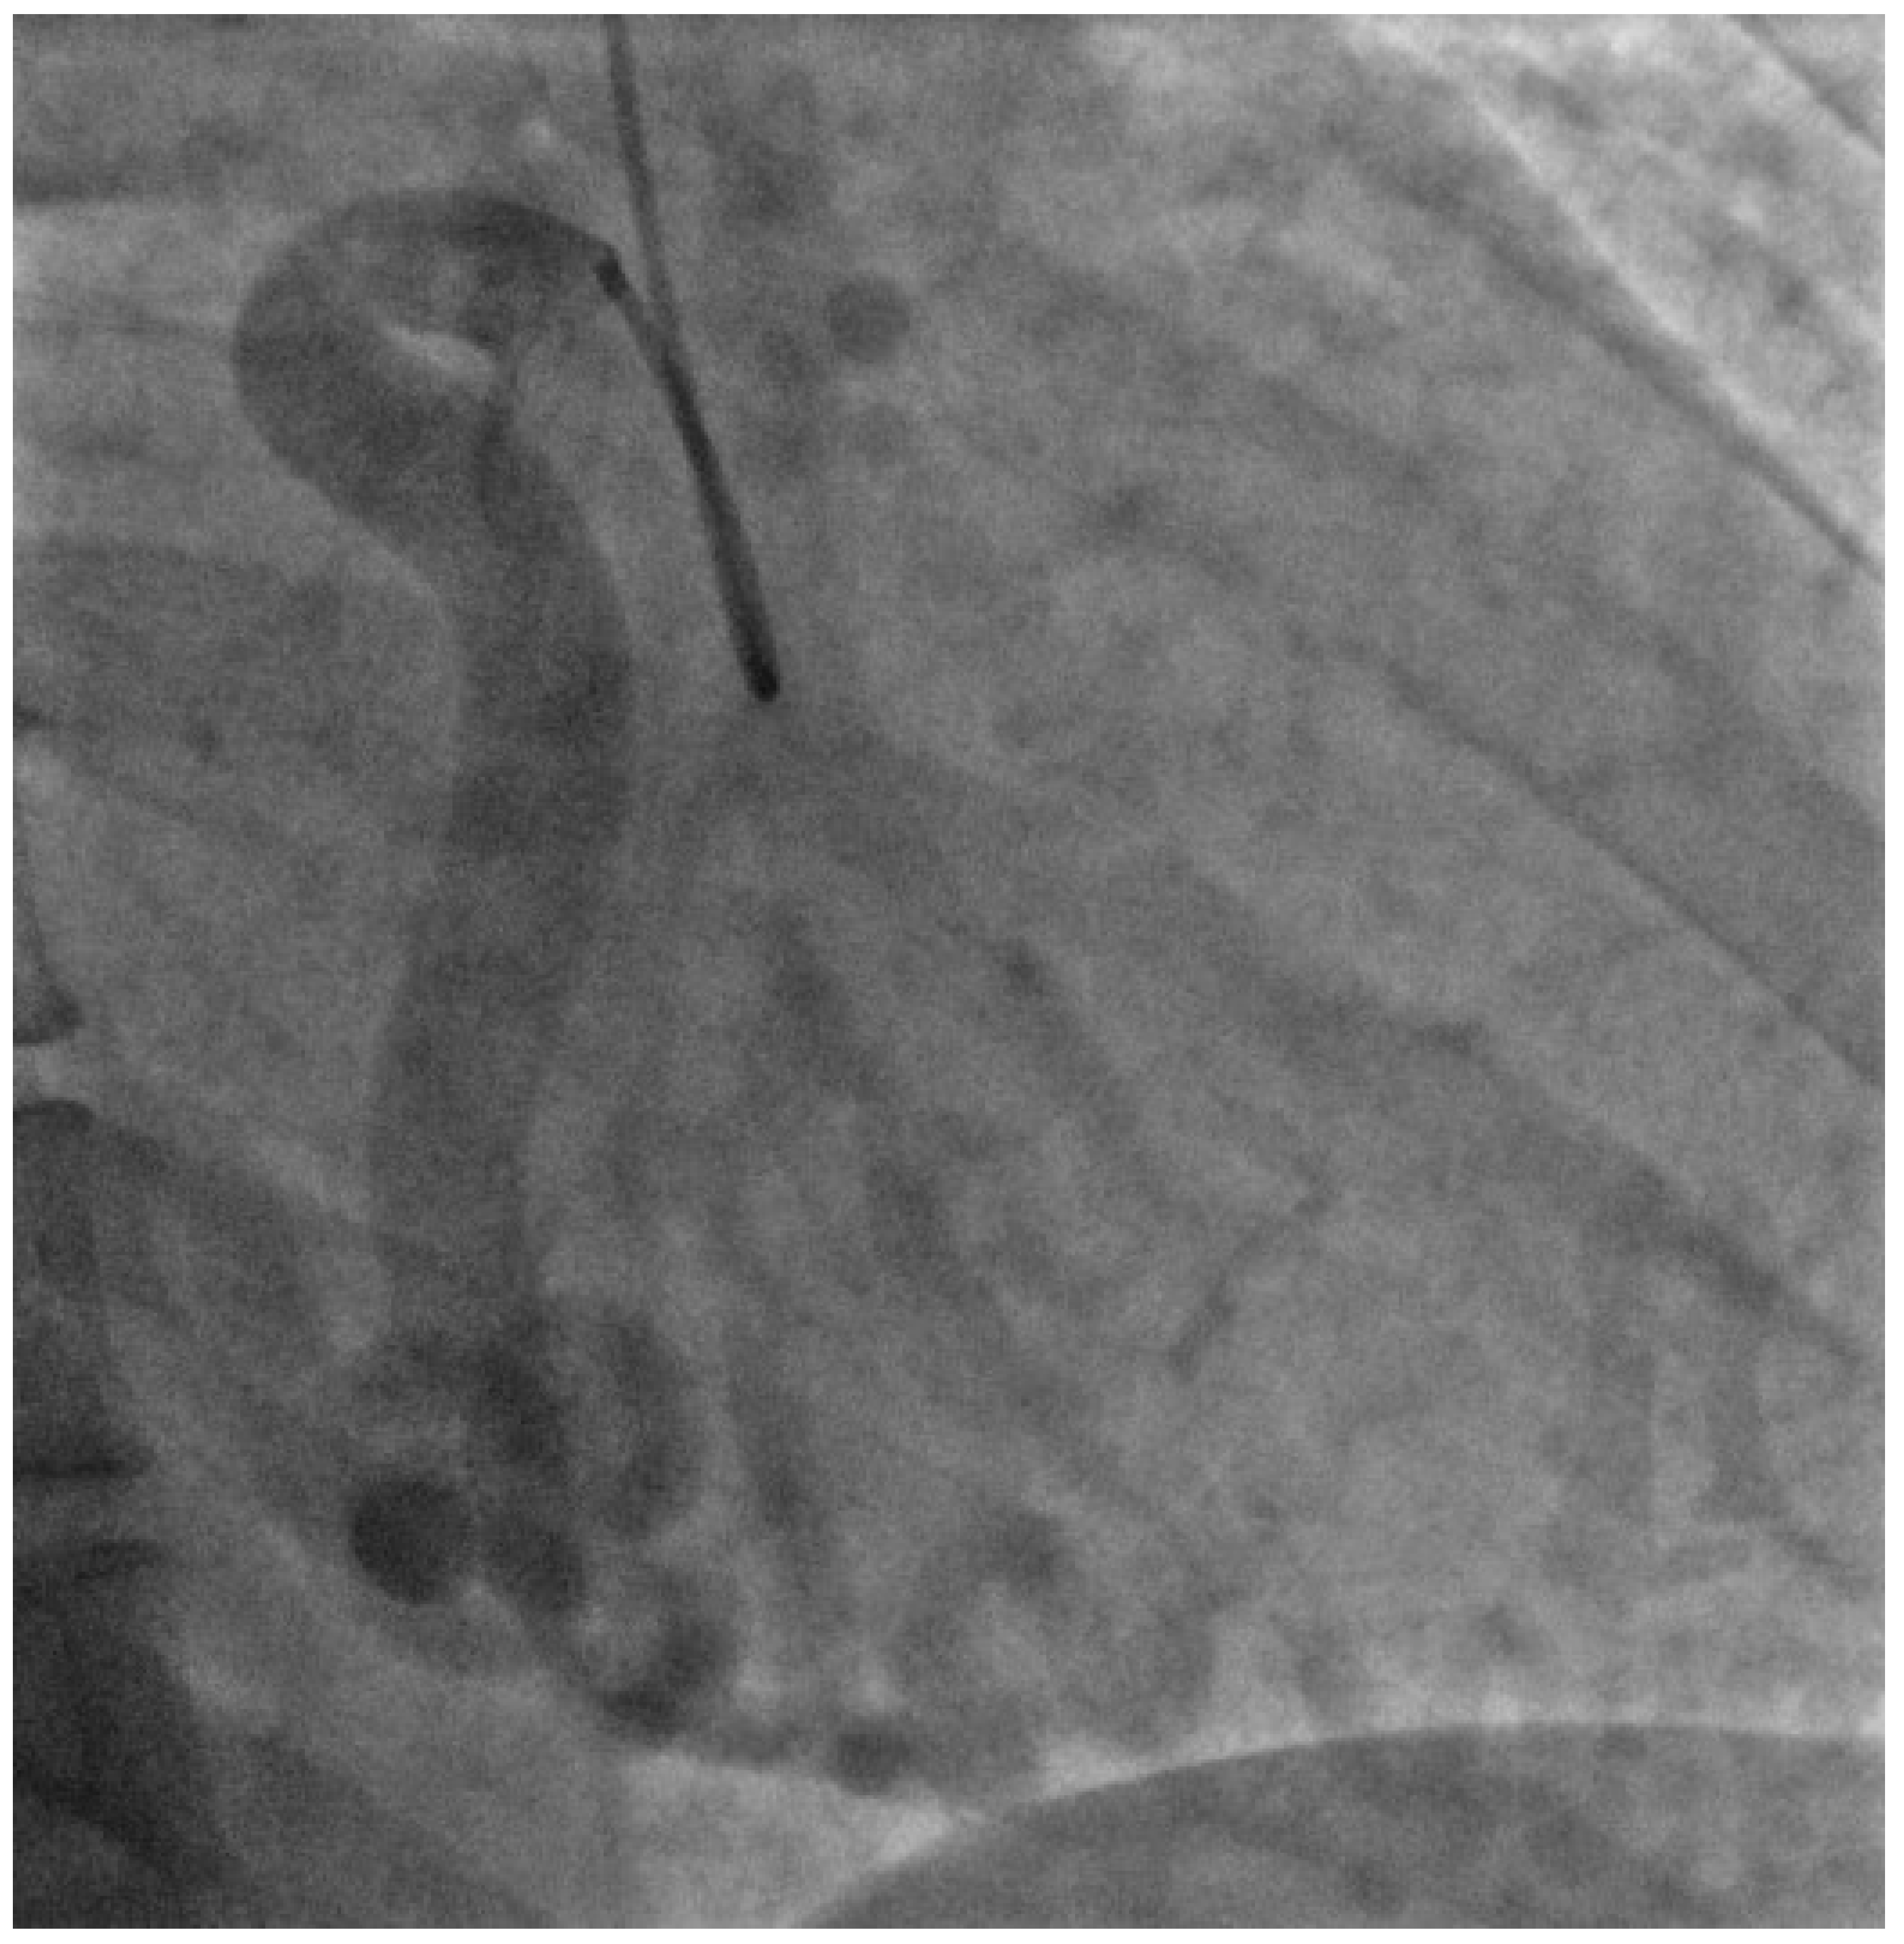

For further assessment, she underwent cardiac Magnetic Resonance Imaging (MRI) to investigate a possible cardiomyopathy. This showed dilatation of the left ventricle and an ejection fraction of 51%. Late gadolinium enhancement sequences also found a previous myocardial infarction in the LAD territory. In view of the cardiac MRI findings, she had a diagnostic coronary angiogram. This showed a large aneurysmal right coronary artery of normal origin but the left coronary artery could not be cannulated, suggesting an aberrant origin (Figure 4).

Figure 4.

Angiographic image of the coronary circulation and collaterals. Right coronary artery appears dilated and tortuous with collaterals following across to the left side of the heart.